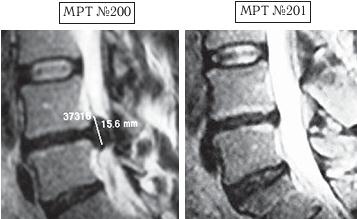

На МРТ № 200 наблюдается состояние поясничного отдела позвоночника после операции: рецидив — секвестрированная грыжа межпозвонкового диска в сегменте LIV-LV, абсолютный стеноз спинномозговогоканала. На МРТ № 201 — состояние поясничного отдела позвоночника после лечения методом вертеброревитологии. |